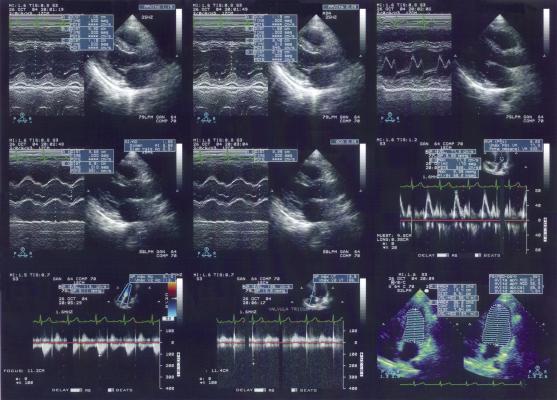

Civco’s EX3 Stepper, like its predecessor the EXII, offers compatibility for BK Medical, GE Healthcare, Hitachi Aloka and Siemens transrectal ultrasound probes, and it is currently validated for use with Varian Vitesse and VariSeed treatment planning software.